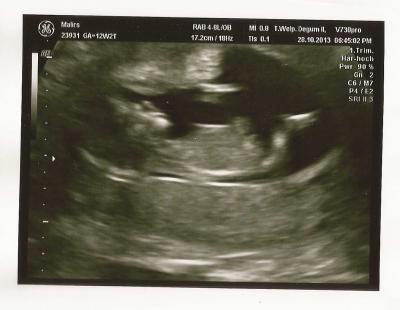

Mit dem Baby ist alles in Ordnung. Nackenfalte entspricht genau dem Wert, wo sie haben sollte... mir gehts nun besser und meine Bauchschmerzen sind weg... Anbei ein Bildchen von unserem Zwerg

Bild zu Nackenfaltenmessung - Forum für Mai - Mamis